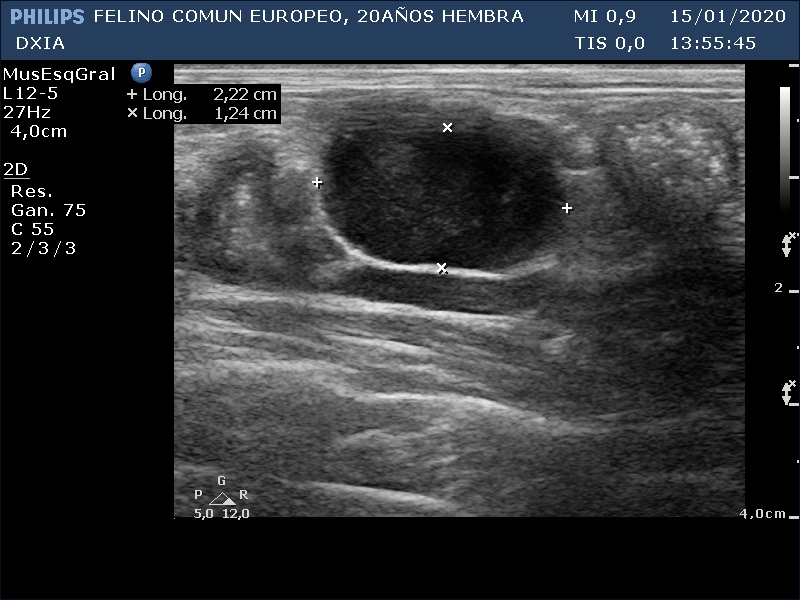

FRANGELICA

Se realiza ecografía y se observa alteración compatible con neoformación en asa del intestino delgado.

Asa del ID con aumento de grosor de su pared, pérdida de estructura en capas. Neoformación hipoecogénica.

Ganglio yeyunal con aspecto globoso, hipoecogénico y bastante homogéneo, índice mayor de 0.5. Compatible con mayor probabilidad con proceso tumoral o metastásico.

Asa del ID con neoformación sin definición de capas intestinales.